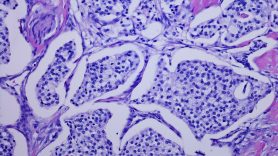

Consensus subtypes of hepatocellular carcinoma may improve treatment selection

Hepatocellular carcinoma (HCC) — the most common type of liver cancer — is a heterogeneous disease composed of different molecular subtypes. A better understanding of these subtypes, based on specific tumor alterations, could improve treatment selection, but there is no uniform system to stratify HCC subgroups. A research team led by Ju-Seog Lee, Ph.D., integrated 16 previously published HCC genomic signatures to identify five consensus subtypes significantly correlated with clinical outcomes. The team characterized the molecular features of each group and demonstrated these features were conserved in laboratory models. They developed a 100-gene signature to classify tumors into a subtype and identified potential blood biomarkers that could be used to stratify patients. These consensus subtypes provide a framework for preclinical studies to identify optimal therapeutic strategies, which could help with selecting more effective therapies for patients in the future. Learn more in Hepatology.